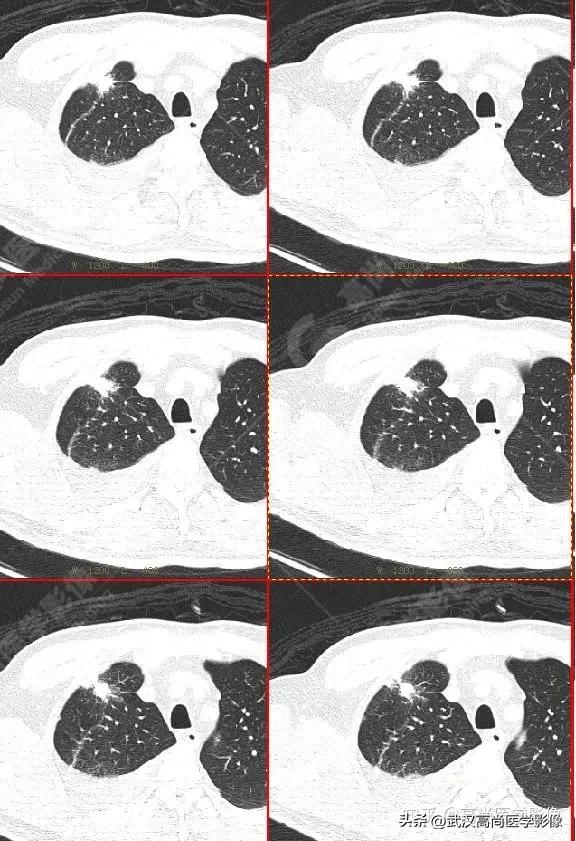

影像表现:

右肺上叶尖段胸膜下见一实性结节,范围约1.6cm×1.3cm,病灶紧贴邻近胸膜,伴牵拉增厚,FDG高摄取,SUVmax为7.5。

恶性CT征象:

结节边缘不光整,分叶、长短不一的毛刺,邻近胸膜牵拉明显。

另外,左肺上叶前段见一团状混杂磨玻璃影,范围约4.3cm×3.3cm,CT值约-662Hu,内部扭曲扩张支气管及血管影穿行,边缘分叶、棘状突起,FDG摄取轻度增高,SUVmax1.3,考虑为多中心起源浸润性肺癌(多原发的肺癌)。